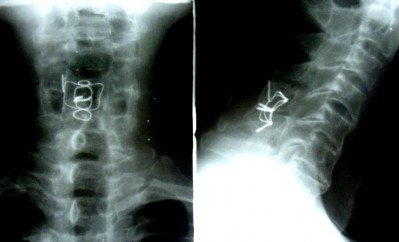

7 NĂM SAU

THẲNG NGHIÊNG

Sau mổ 7 năm: tình trạng chỉ KHX vẫn tốt. Liền xương độ I. Không di lệch thứ phát